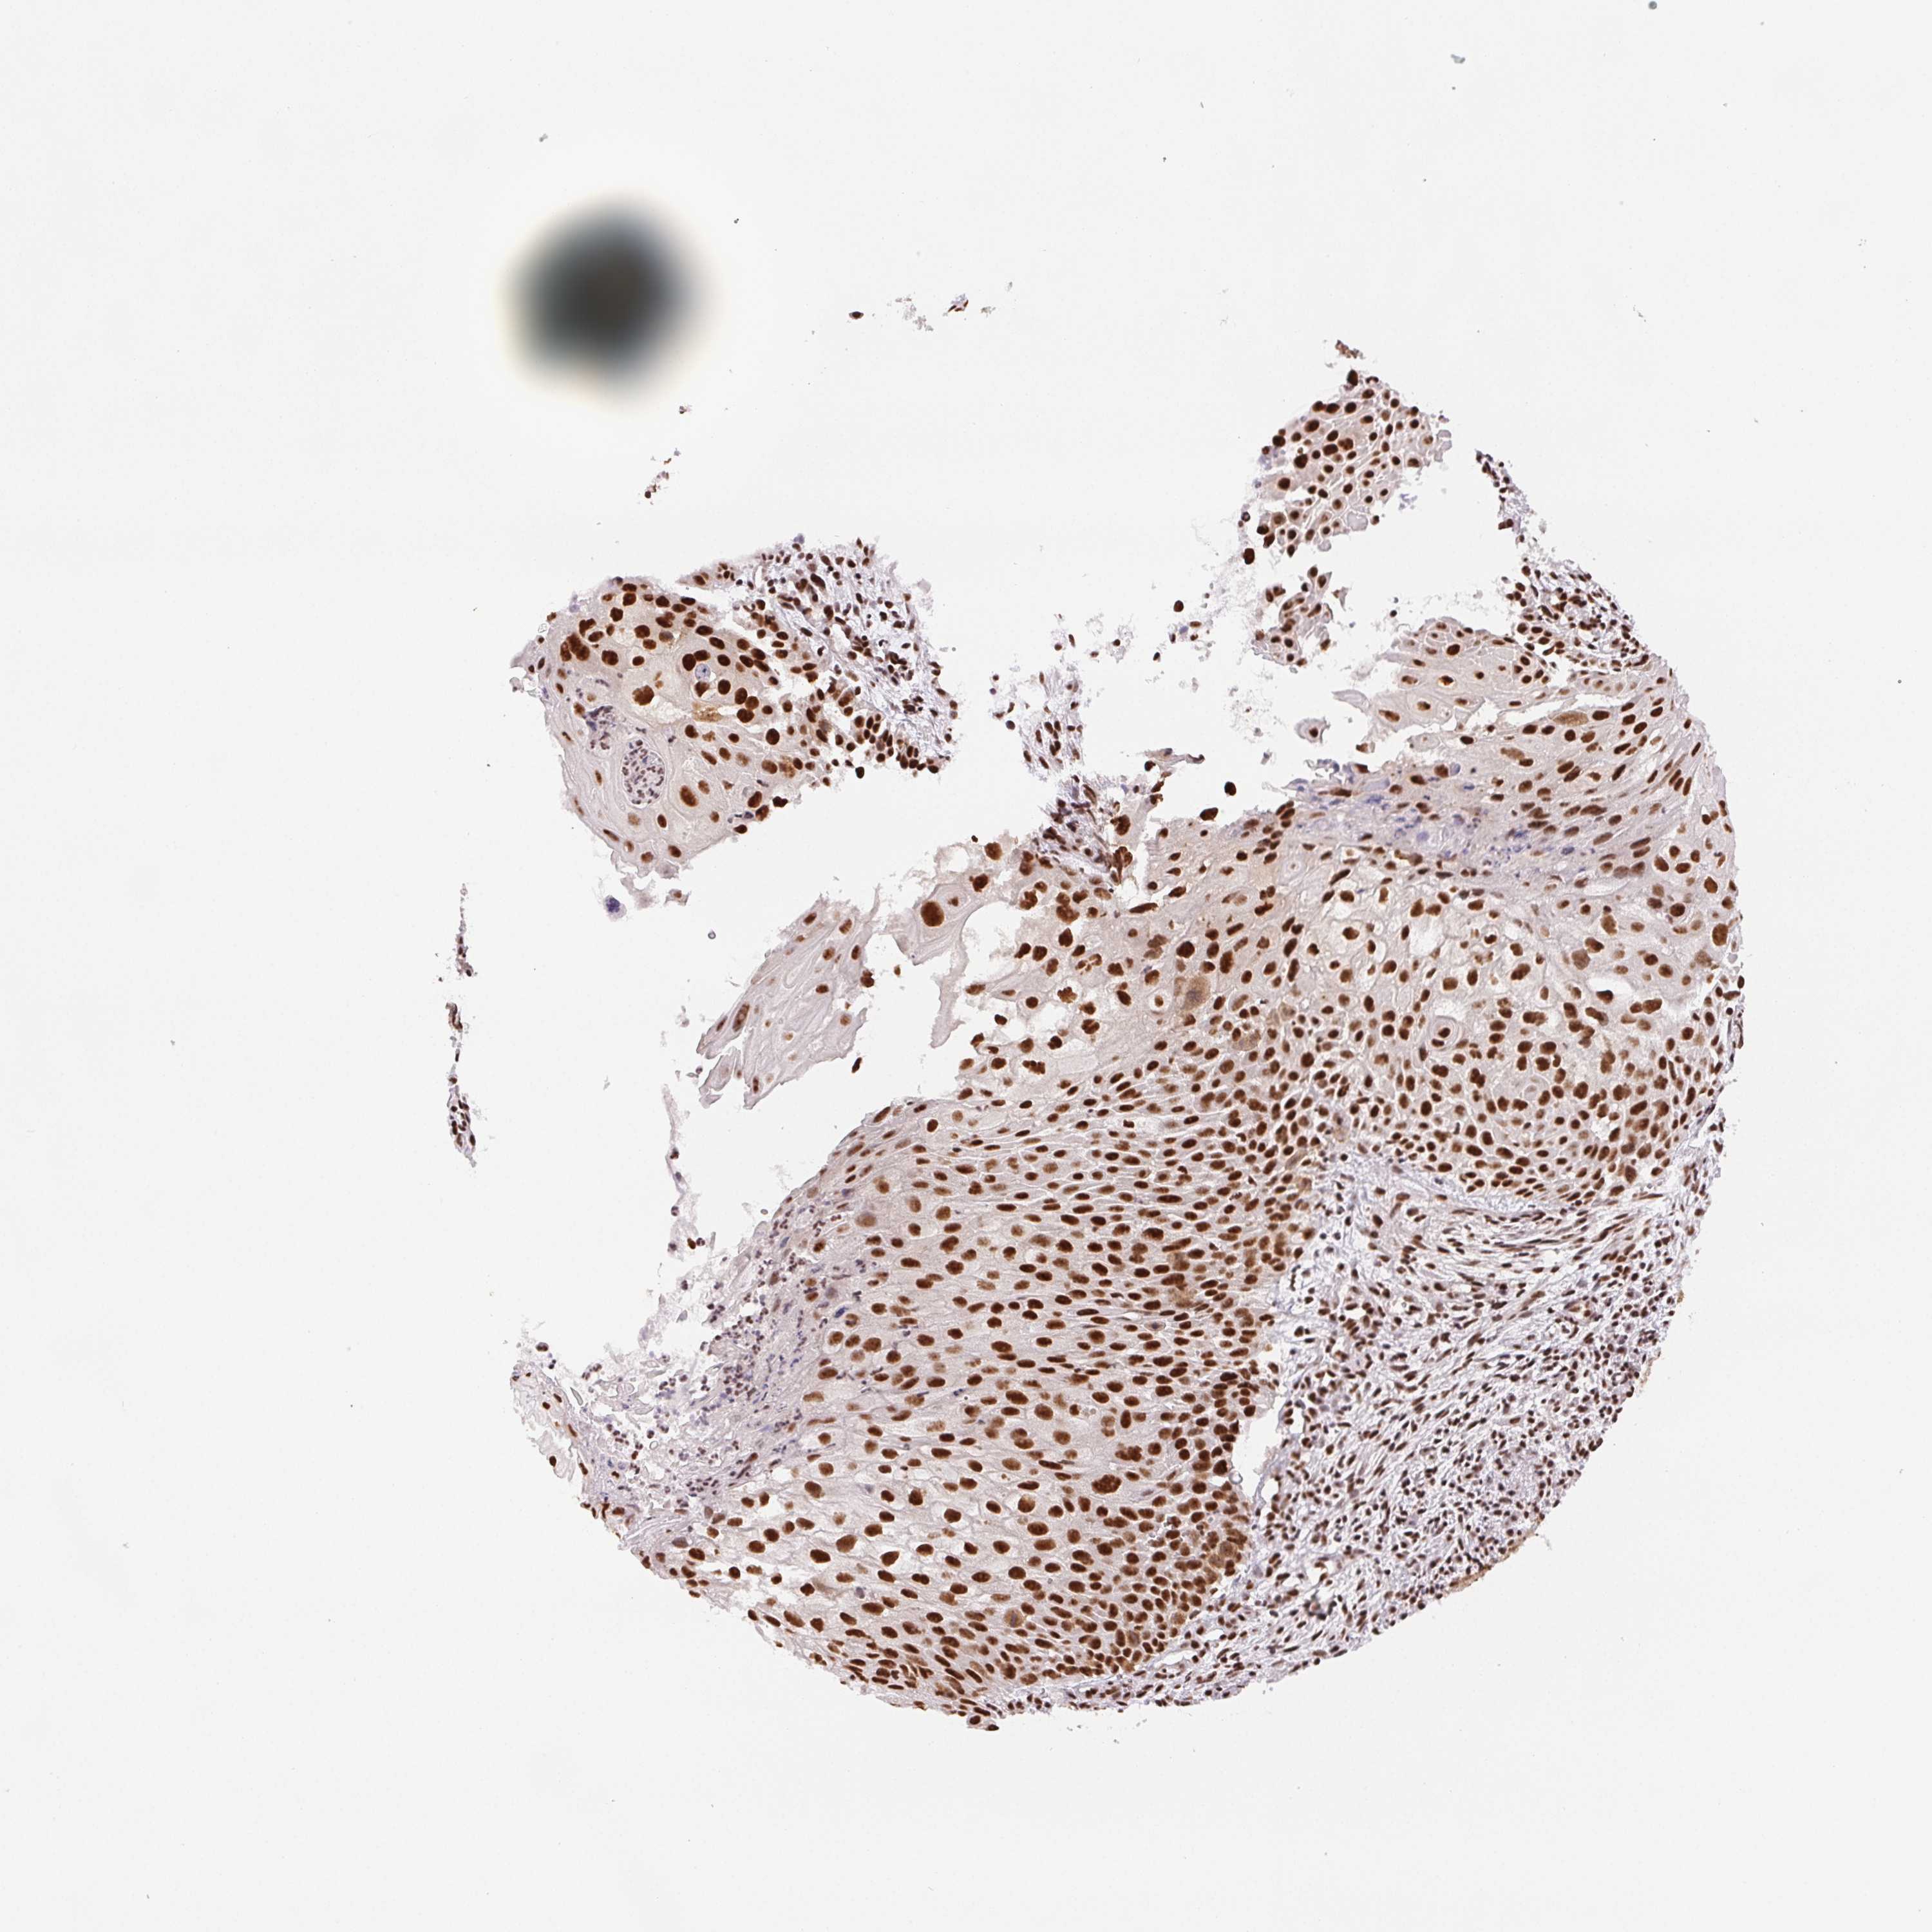

CERVICAL CANCER - Protein expressioni

A mouse-over function shows sample information and annotation data. Click on an image to view it in a full screen mode. Samples can be filtered based on level of antibody staining by selecting one or several of the following categories: high, medium, low and not detected. The assay and annotation is described here.

Note that samples used for immunohistochemistry by the Human Protein Atlas do not correspond to samples in the TCGA dataset.

Antibody stainingi

Antibody staining in the annotated cell types in the current human tissue is reported as not detected, low, medium, or high, based on conventional immunohistochemistry profiling in selected tissues. This score is based on the combination of the staining intensity and fraction of stained cells.

Each image is clickable and will lead to virtual microscopy that enables deeper exploration of all samples and also displays staining intensity scores, fraction scores and subcellular localization as well as patient and tissue information for each sample.

Antibody HPA048798

Staining

High

Medium

Low

Not detected

Intensity

Strong

Moderate

Weak

Negative

Quantity

>75%

75%-25%

<25%

None

Location

Nuclear

Cytoplasmic/membranous

Cytoplasmic/membranous,nuclear

Squamous cell carcinoma, NOS

Adenocarcinoma, NOS